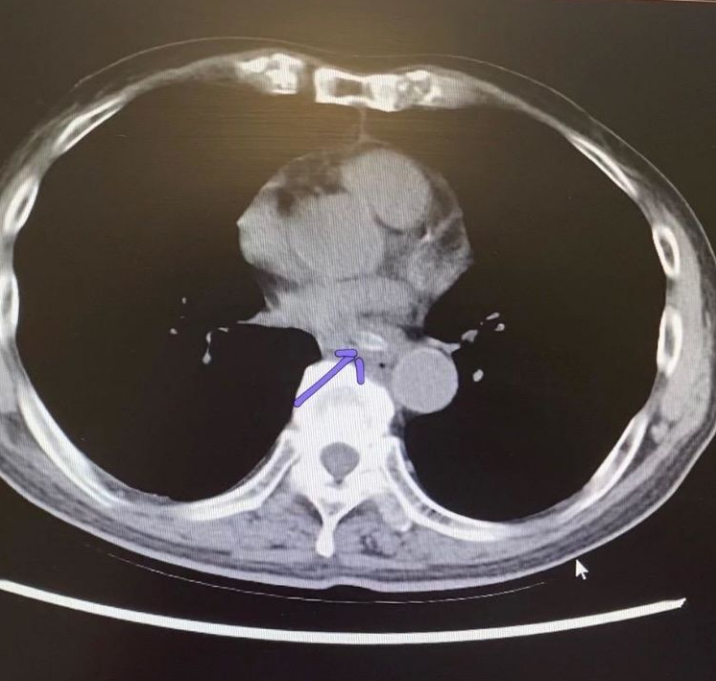

▲王大爺?shù)男夭緾T提示:食管下段可見(jiàn)一異物嵌頓

科主任李小會(huì)考慮異物已在患者食管內(nèi)存在數(shù)天,棗核會(huì)隨著吃飯、說(shuō)話甚至吞咽動(dòng)作而越嵌越深,導(dǎo)致食管穿孔的風(fēng)險(xiǎn)極大,且該棗核嵌頓的位置緊鄰胸主動(dòng)脈,如果刺破這根大血管,將導(dǎo)致致命性的大出血,后果不堪設(shè)想。為保證手術(shù)的順利實(shí)施,李小會(huì)在制定治療策略的同時(shí),請(qǐng)心胸外科黃華元主任前來(lái)會(huì)診,最終決定在內(nèi)鏡下為王大爺取異物:如果出現(xiàn)食管穿孔,可以在取出棗核后置入食管覆膜支架;若棗核穿孔入大血管,則可于大血管內(nèi)植入覆膜支架進(jìn)行血管修補(bǔ)后,再行異物移除操作。